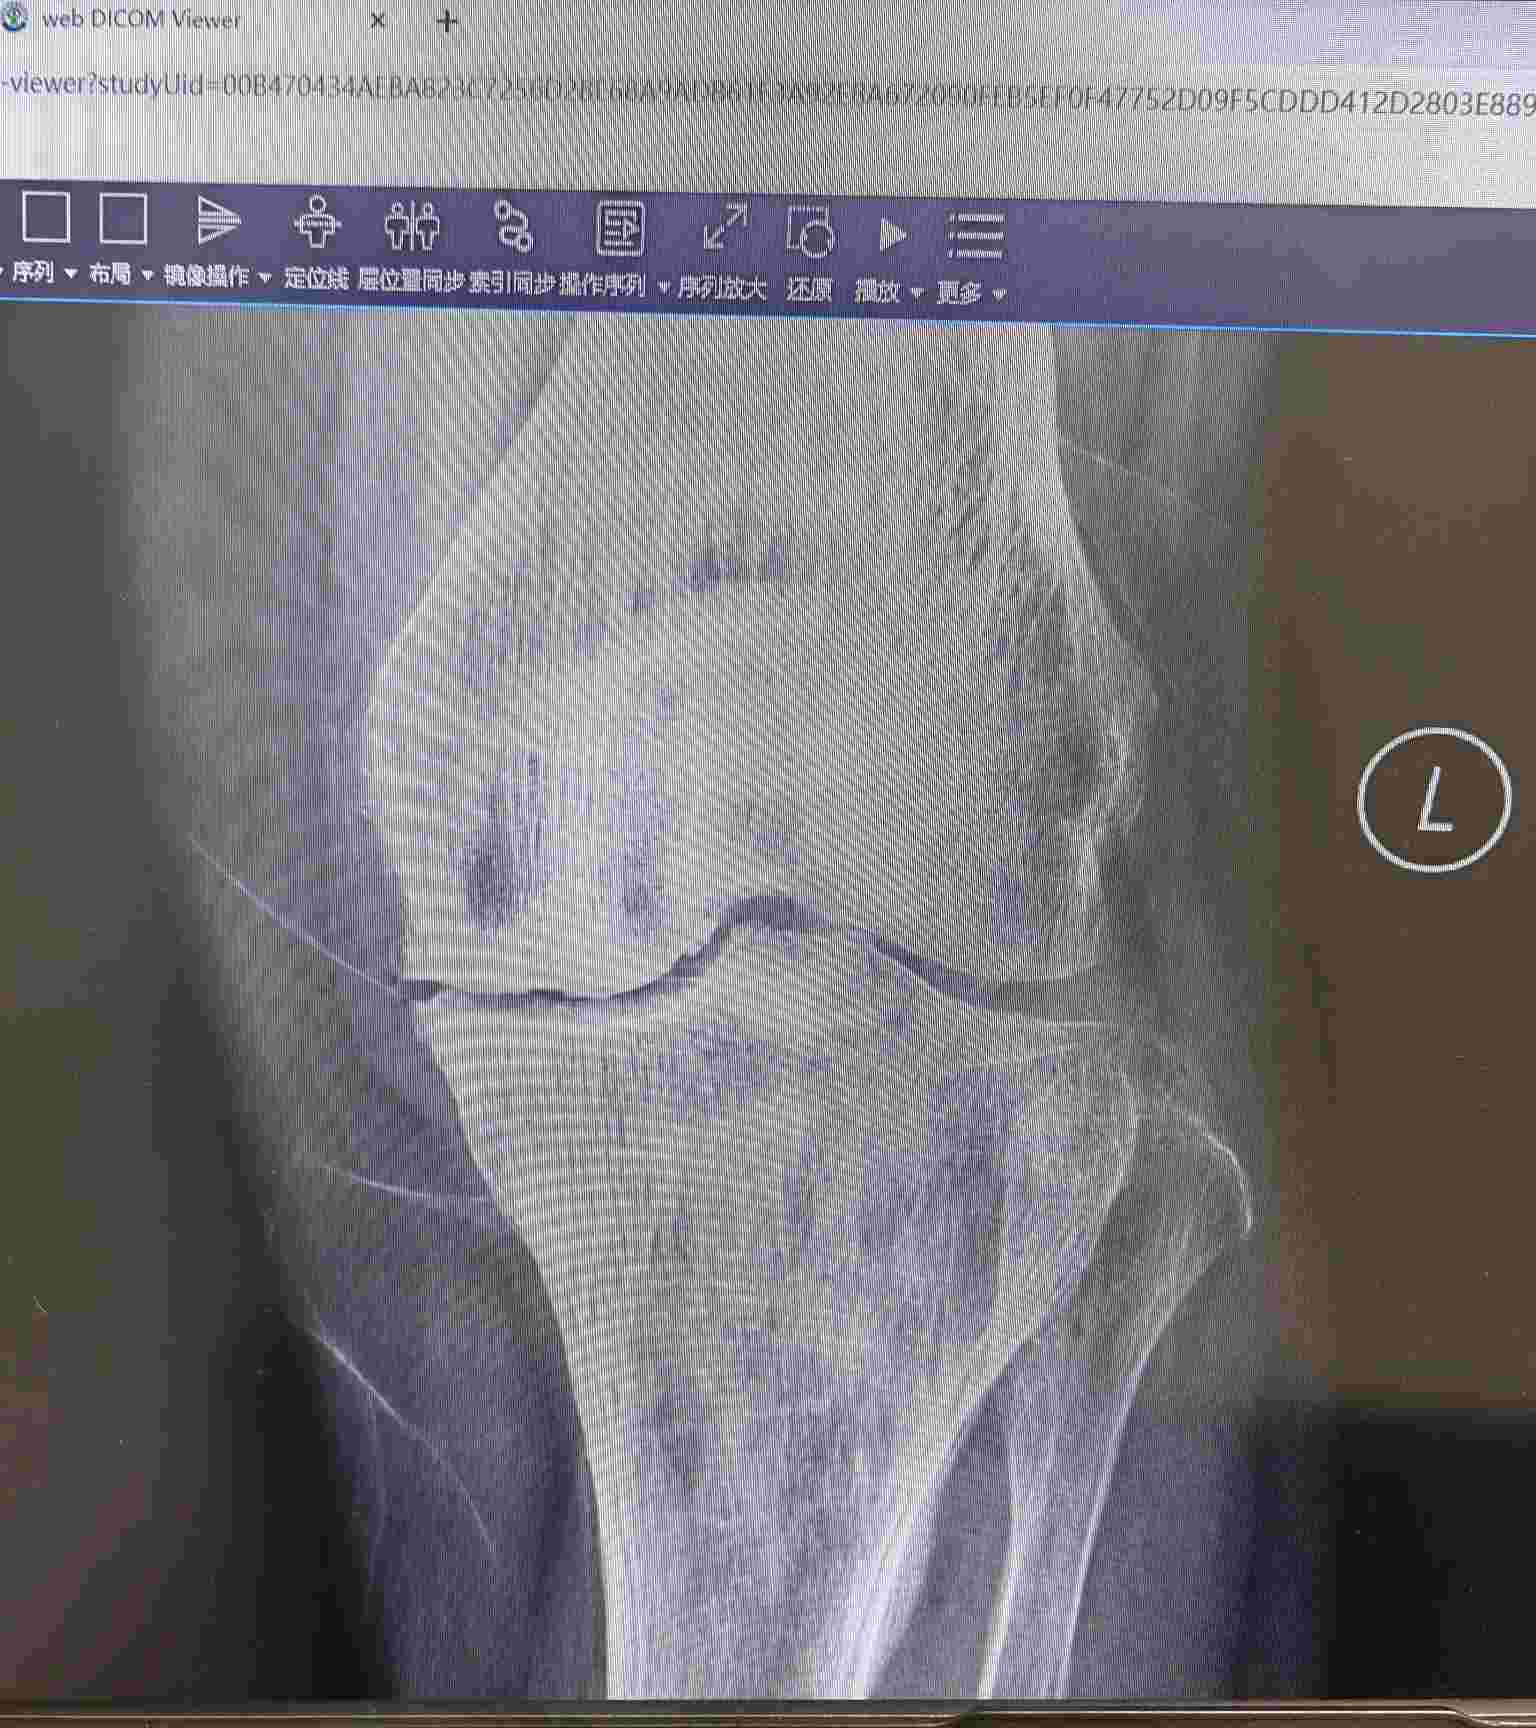

· 关节间隙变窄: 软骨磨没了,关节之间的缝隙就变窄了。这在X光片上是诊断的重要依据。

1. 明确诊断: 如果您怀疑自己有膝关节退行性变,请首先去骨科或关节外科就诊,通过医生体格检查和X光片(必要时做核磁共振MRI)来明确诊断和分期。